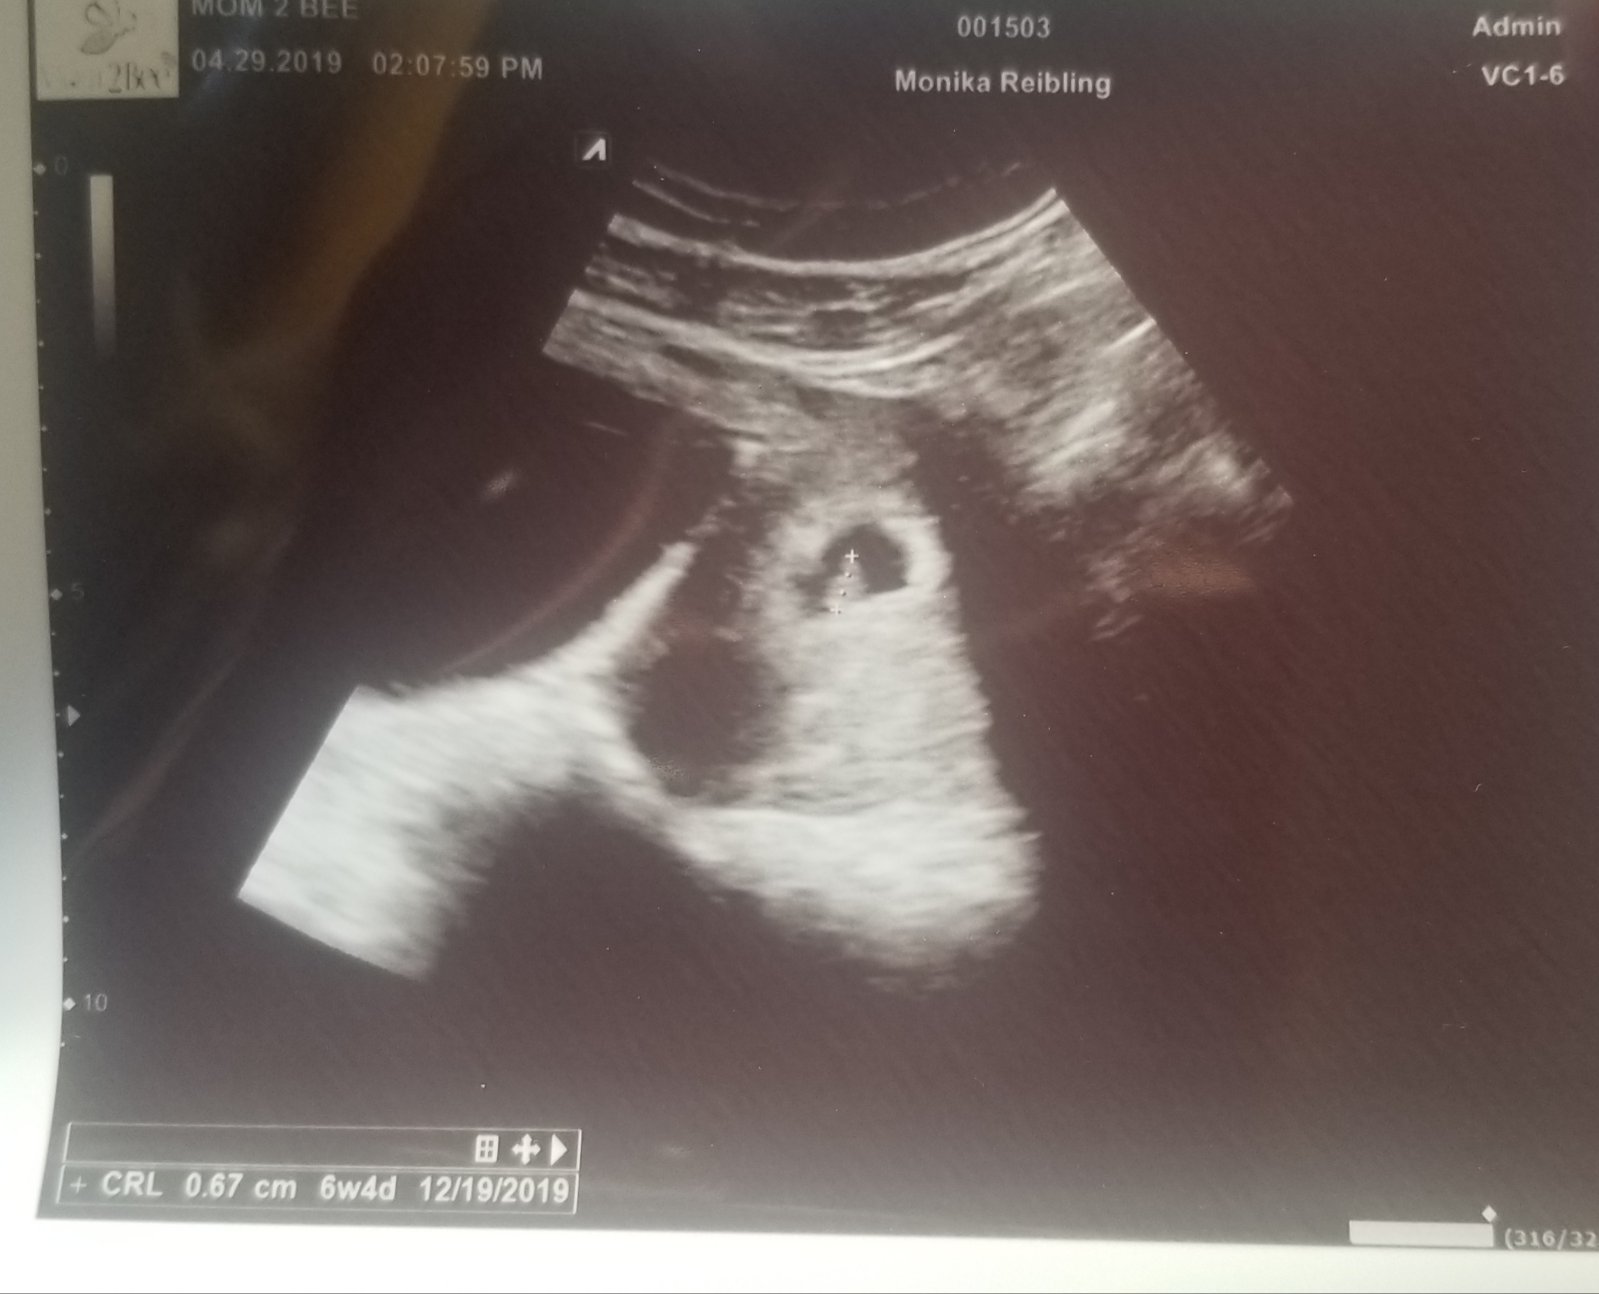

@lostris151 tak ako si dopadla ?už máš aj ty fotecku?

@lostris151 supeeer gratulujeeeeem ❤️teším sa s tebou 😘ja si ešte musím pockat🙏💞✊

@lostris151 jeej no super 🙂 tak si sa dočkala aj ty 🙂 😍 je to pravda 😘 a za chvíľku čakáme aj tvoju fotecku @lilly79

Dakujem babenky 😍 je to rozhodne ulava 🙂 @lilly79 presne viem ako sa citis a neboj sa coskoro to budes mat aj ty za sebou a budes moct kludne tehulkovat ;)

@lilly79 ja som asi len 4 dni po zuzu teraz 6+5tt, dalsi usg mam 13.5 ten oficialny v nemocnici a potom by som mala dostat termin ku gynekologovi ale do Halifaxu z nejakeho dovodu, ako ok hlavne mesto tak snad kvalita vyssia ale neviem si predstavit ze pojdem rodit 1.5h od domu 🤷♀️ ale tak hlavne je aby som sa k tomu dopracovala a vsetko bolo ok a snad nebudem ako segra rodit v aute 😁😳